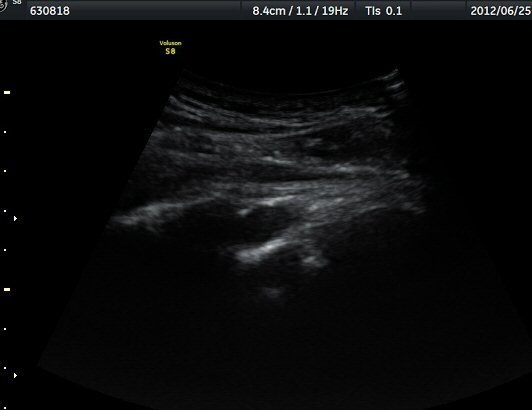

¾î±ú °üÀý µÚÂÊ ÈĹæ°üÀý¼ø Ⱦ´Ü¸é°Ë»ç¿¡¼­ °üÀý¼ø ³»Ãø, °¡½Ãµ¹±â°üÀý¼ø°í¶û(spinoglenoid

notch)¿¡¼­ Àú¿¡ÄÚ ³¶Á¾ÀÌ °üÂûµÈ´Ù(±×¸² 1). ŽÃËÀÚ¸¦ À§-¾Æ·¡ ¹æÇâÀ¸·Î º¯°æÇÏ¿© °üÂûÇÒ ¶§µµ

¿ª½Ã °ß°©°ñ °¡½Ãµ¹±â(spine) ¾Æ·¡¿¡¼­ Àú¿¡ÄÚ ³¶Á¾ÀÌ °üÂûµÈ´Ù(±×¸² 2). º¼·ÏŽÃËÀÚ·Î ¹Ù²Ù¾î °ü

ÂûÇÏ´Ï  °¡½Ãµ¹±â°üÀý¼ø°í¶û¿¡¼­ Àú¿¡ÄÚ ³¶Á¾ÀÌ ´õ¿í ¶Ñ·ÈÈ÷ °üÂûµÈ´Ù(±×¸² 3, 4).